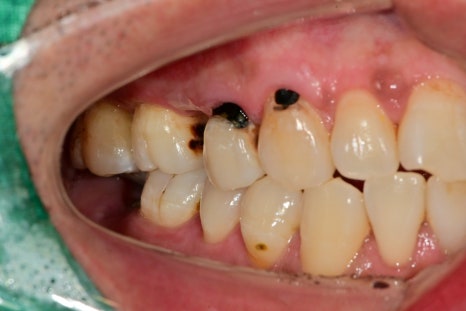

엑스레이, 구강 내 사진을 보게 되면 여러 종류의 치료가 필요한 부위들이 보입니다

충치로 인한 심미적인 부분, 치아 상실 부위, 대합 치아가 없다 보니 아래로 내려온 치아,

깊은 충치로 인한 신경치료가 필요한 치아까지

좌우 다수의 치아에서 치료가 필요했습니다.

앞니 쪽의 새까맣던 충치 부위도 치아색에 맞춰서 레진 치료까지 마무리되었습니다

범위가 너무 넓으면 크라운치료가 필요한 경우가 있지만

레진으로도 충분히 치료가 가능해 보였기 때문에

최대한 치아색에 맞춰서 치료를 했습니다.